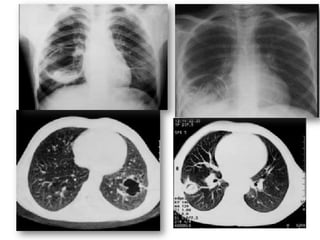

• Stade IV:

• images hydroaériques d’aspect variable

- Nénuphar +++ ( ds 10% rupture)

Aspect de membrane flottante surnageant la surface ou immergée

dans le liquide

- Opacités avec image de niveau hydroaérique

rectiligne

- Image en double arc d’Ivassinevitch, réalisée par la

superposition de deux épanchements gazeux l’un intra-kystique et

l’autre intra-adventiciel séparés par la membrane flétrie de

l’hydatidose

• Stade V: stade séquellaire

• Aspect radiologique variable selon le degré de

l’évacuation du kyste:

- Image d’incarcération des membranes .

- Image de membrane pelotonnée

- Image en cocarde , en grelot

• Stade VI:Calcification :

- dépôts calcaires sur adventice , signes

radiologiques caractéristiques»image en

coquille d’œuf »

- La calcification ne traduit pas la dégénérescence

du kyste.

- Exceptionnelle au niveau des poumons

3.2.2.Examens paracliniques

imagerie thoracique

a.2. Tomodensitométrie thoracique

• Pas indispensable au diagnostic de kyste

hydatique du poumon

• Utile dans le bilan lésionnel pré opératoire.

• Analyse paroi du kyste, topographie, rapports

avec bronches et structures vasculaires.